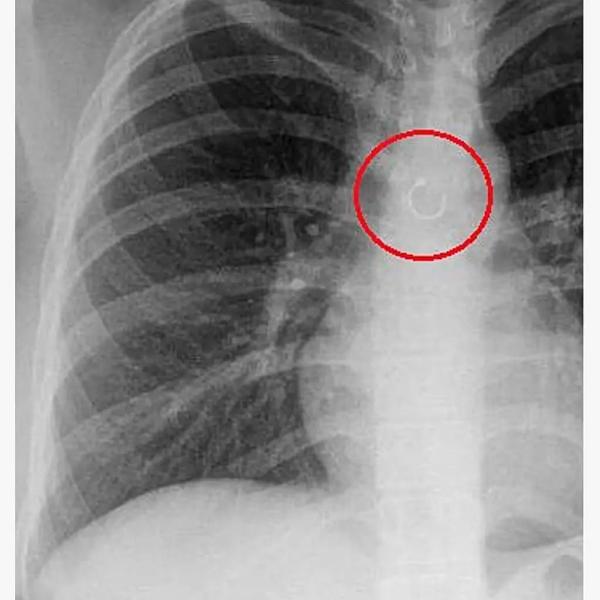

26-летняя девушка рассказала, что внезапно стала страдать от постоянного кашля. Сначала она списала его на изменение погоды в ее родном штате Нуэво-Леон, но спустя месяц все же обратилась к врачу. Во время обследования в легком Барахас нашли металлическое кольцо — пирсинг из ее носа.

Пирсинг удалили из легкого девушки хирургическим путем. Врачам потребовалось две операции, чтобы добраться до него. Оказалось, что кольцо находилось в 0,5 миллиметра от аорты и могло пробить ее. Это было бы смертельно.